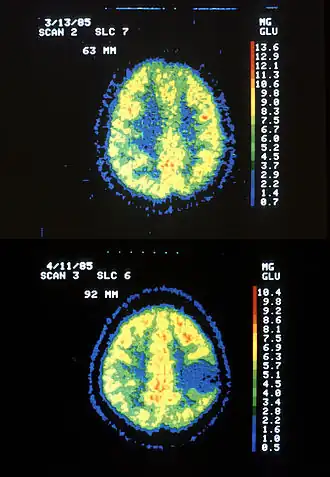

Scanner IRM d'un patient atteint d'un astrocytome montrant l'évolution sur 7 ans.